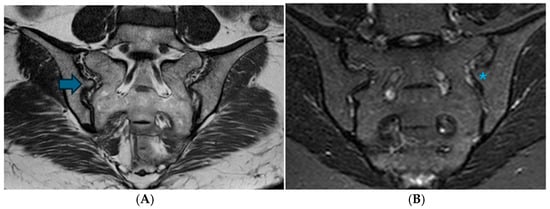

Assessment of Anatomical Variations in the Sacroiliac Joint Using Magnetic Resonance Imaging: A Retrospective Study of 840 Patients

Background/Objectives: This study aimed to examine the prevalence of anatomical variations in the sacroiliac joints (SIJs) as observed through Magnetic Resonance Imaging (MRI), to characterize their manifestations, and to identify MRI features that may resemble inflammatory alterations. Methods: A retrospective review was conducted on consecutive MRI scans of the SIJ performed from January 2009 to January 2022. Eight anatomical variations, along with associated edematous and structural changes, were assessed. Results: The study encompassed 840 patients, with anatomical variations identified in 39.7% of the cohort, occurring more frequently among female participants. The most prevalent variations were accessory SIJ (36.2%) and the iliosacral complex (32.2%). Notably, isolated synostosis and persistent ossification center variations were absent. The increased frequency of variations in women, as well as their correlation with advancing age, was statistically significant (p = 0.034). Accessory SIJ and dysmorphic alterations were linked to bone marrow edema and structural modifications. In the iliosacral complex and semicircular defect variations, prominent vascular structures were observed extending along the bone surfaces. The number and depth of edema slices in sacroiliitis exceeded those observed in the variation (p < 0.001). Conclusions: Anatomical variations of the SIJ are prevalent among women and tend to increase with advancing age. Given that these variations, particularly accessory SIJ and dysmorphic alterations, may present with edematous and structural signal intensity changes that resemble sacroiliitis, it is crucial to recognize these variations. It is recommended to assess axial and coronal images concurrently and to exercise caution in the interpretation of SIJ MR images. Full article

Show Figures

Figure 1